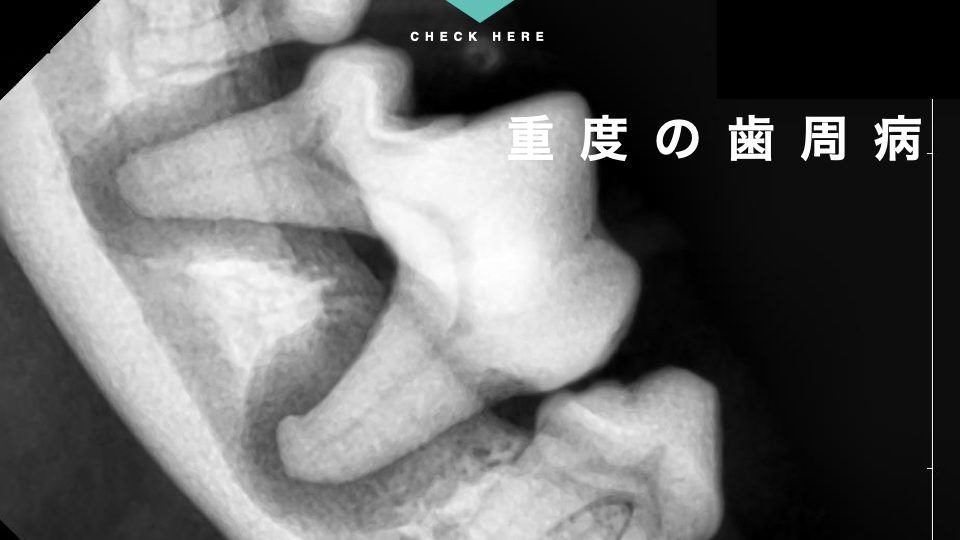

全身麻酔下で歯科レントゲン検査をしてみると、この歯は重度の歯周病が進行していることが分かりました。

対側の歯と比べてみると、歯の根っこを支える歯槽骨が黒く抜けた骨吸収が起こってしまっています。

この子のような小型犬で顎が小さい子は、こうした歯周病の進行による骨吸収で下顎骨の病的骨折を引き起こしてしまうリスクがあります。